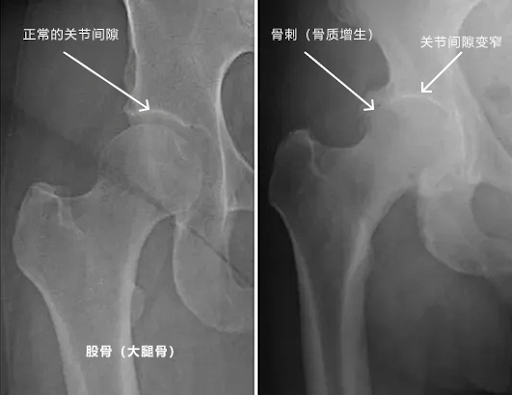

这是一个最大的误区。虽然它叫“骨刺”(Bone Spurs / Osteophytes),但在X光下,它通常看起来是表面光滑的凸起,而不是尖锐的针 。

骨刺其实是骨骼的一种“自我保护机制”。当您的关节因为老化、长期受力不均或软骨磨损(关节炎)变得不稳定时,身体为了增加接触面积来稳定关节,就会长出额外的骨质 。